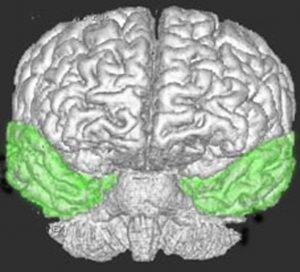

側頭葉の解剖図

側頭葉の解剖図です

側頭葉の解剖図です。表面からは見えませんが,深部の海馬というところには記憶の中枢があります。左側頭葉には言語の中枢もあります。聴覚や味覚,情動などの中枢も側頭葉にあります。

脳の右と左側面から